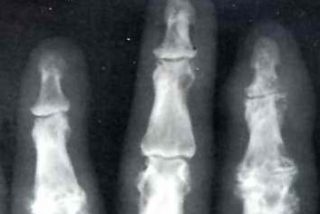

Radiografía

Descubren los genes que inciden en el riesgo de padecer gota

Un equipo de científicos estadounidenses descubrieron los tres genes que pueden incrementar el riesgo de padecer gota, según publica hoy la revista médica británica "The Lancet". La investigación fue dirigida por la doctora Caroline Fox, del Instituto Nacional de Enfermedades Cardíacas, Pulmonares y Sanguíneas de Bethesda, Estados Unidos, la que concluyó que el "riesgo genético" asociado a